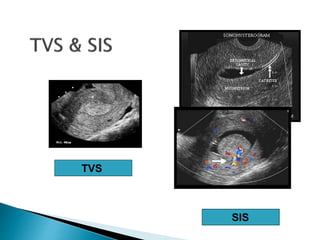

TVS

SIS

 To assess for thickened endometrium

 In 92% of abnormal endometrial biopsies,

ultrasound showed >5mm endometrium

 In 96% of endometrial cancer by biopsy result,

 Therefore, ultrasound measured endometrium

<5mm is likely benign uterine condition